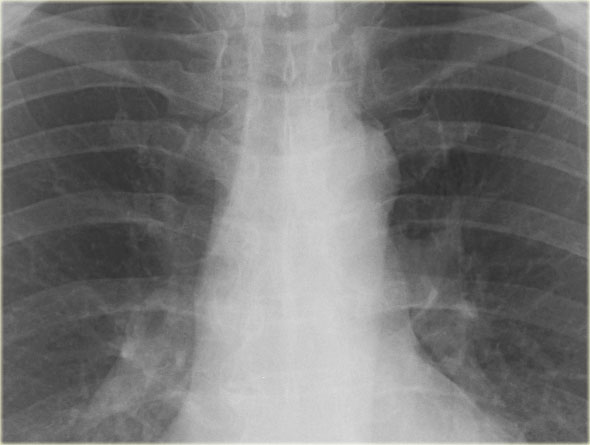

Bên trái là hình ảnh một bệnh nhân khác với phù phế nang lúc nhập viện, đã được giải quyết sau điều trị.

Khi bạn cuộn qua các hình ảnh và so sánh qua lại, bạn sẽ nhận thấy sự khác biệt về độ rộng cuống mạch máu và sự phân bố lưu lượng máu phổi.